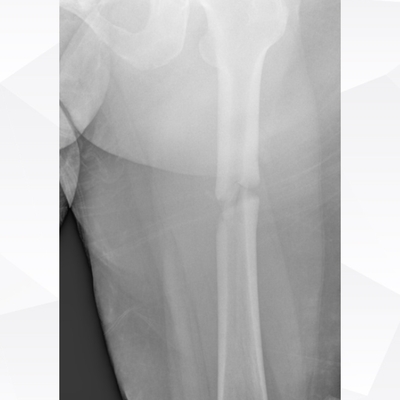

Click on an image below to view more info.